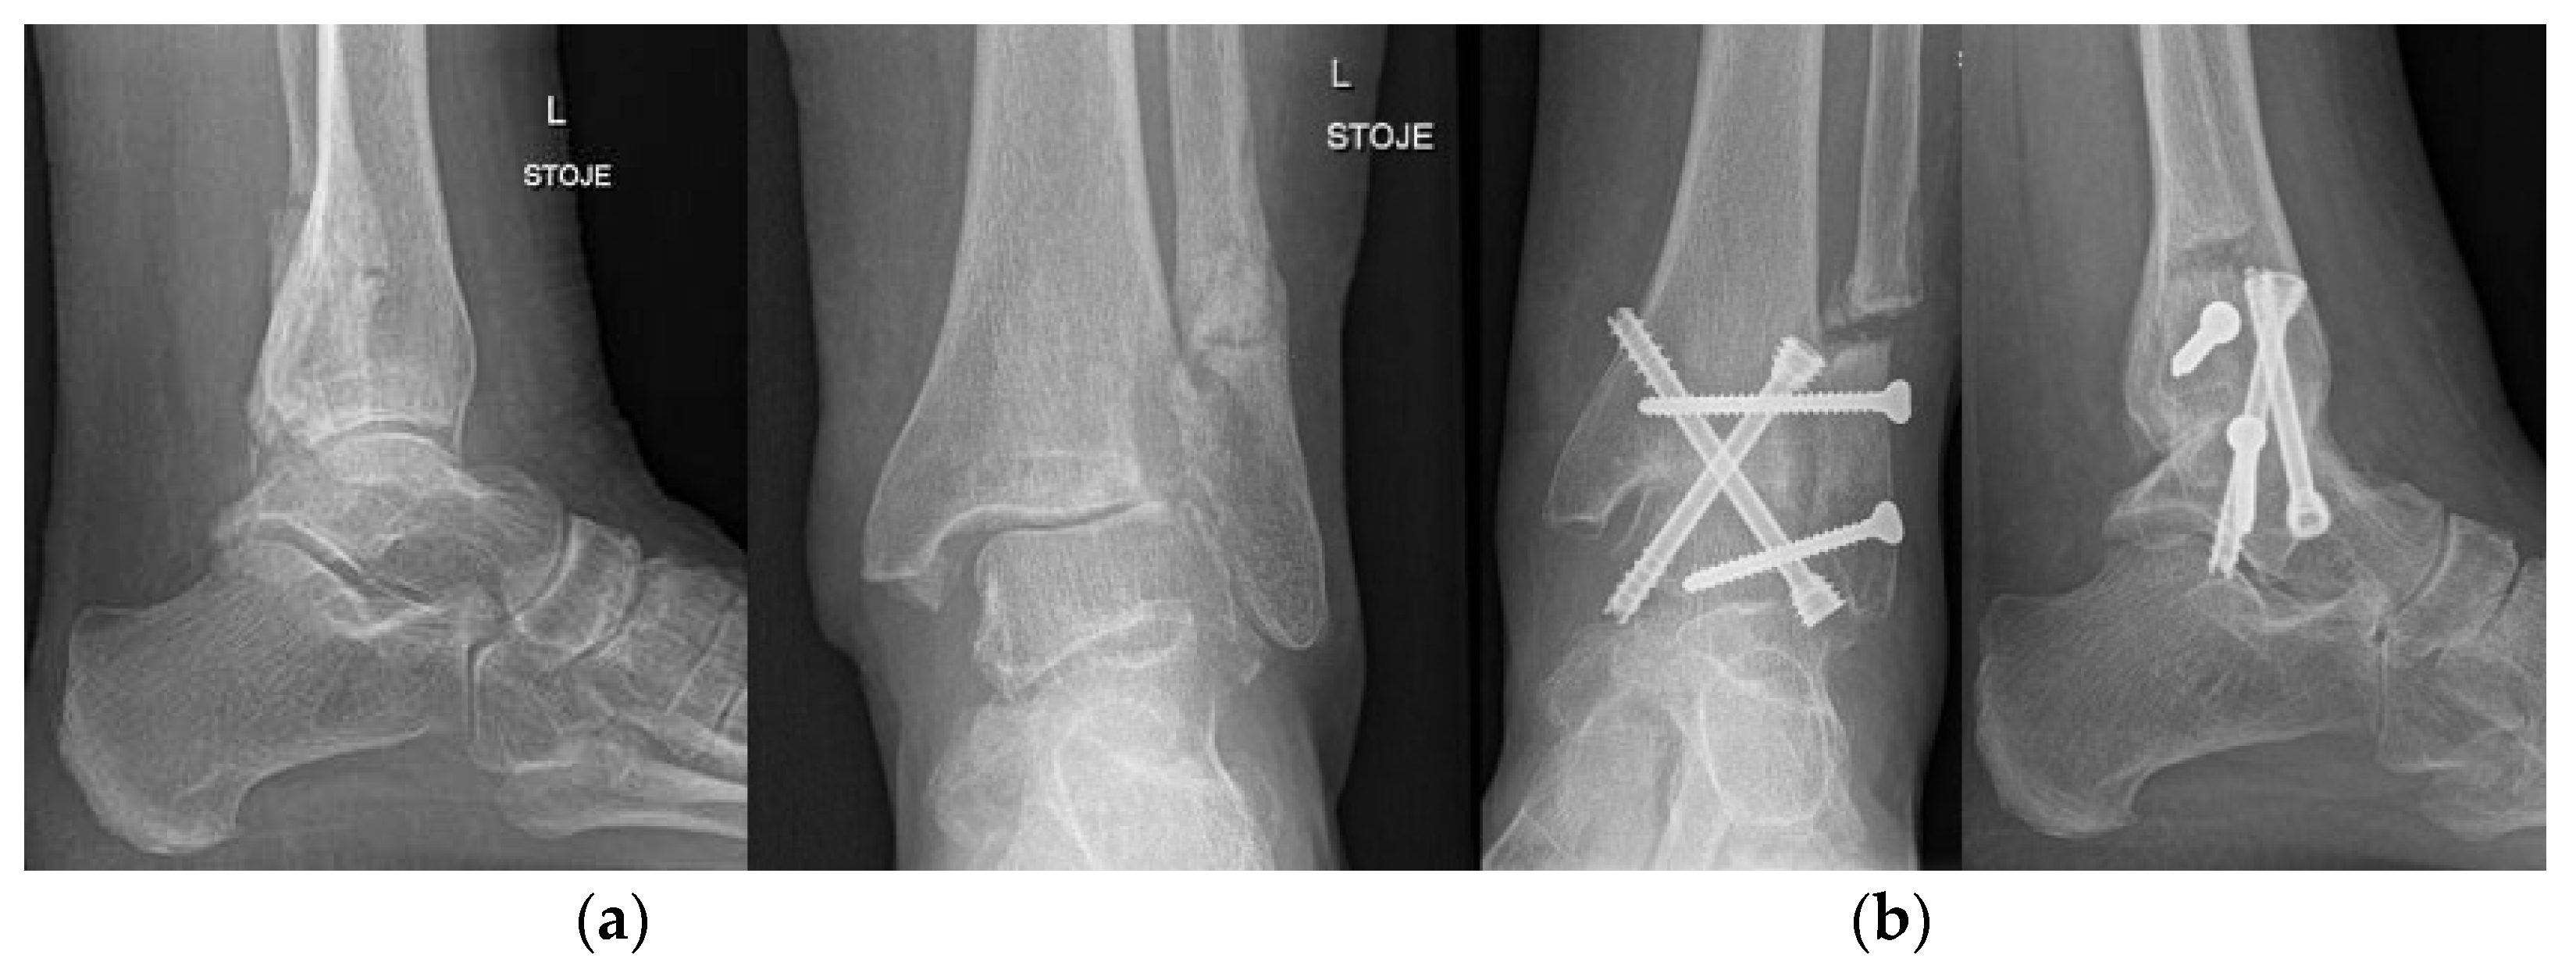

4.7. Ankle and Foot

- Duan, X.; Yang, L.; Yin, L. Arthroscopic Arthrodesis for Ankle Arthritis without Bone Graft. J. Orthop. Surg. 2016, 11, 154. [Google Scholar] [CrossRef] [PubMed]

- Cottino, U.; Collo, G.; Morino, L.; Cosentino, A.; Gallina, V.; Deregibus, M.; Tellini, A. Arthroscopic Ankle Arthrodesis: A Review. Curr. Rev. Musculoskelet. Med. 2012, 5, 151–155. [Google Scholar] [CrossRef]

- Mangwani, J.; Afifi, H.; Faroug, R. Arthroscopic Ankle Arthrodesis—Surgical Technique. J. Arthrosc. Surg. Sports Med. 2021, 2, 135–140. [Google Scholar] [CrossRef]

- Roussignol, X. Arthroscopic Tibiotalar and Subtalar Joint Arthrodesis. Orthop. Traumatol. Surg. Res. OTSR 2016, 102, S195–S203. [Google Scholar] [CrossRef] [PubMed]